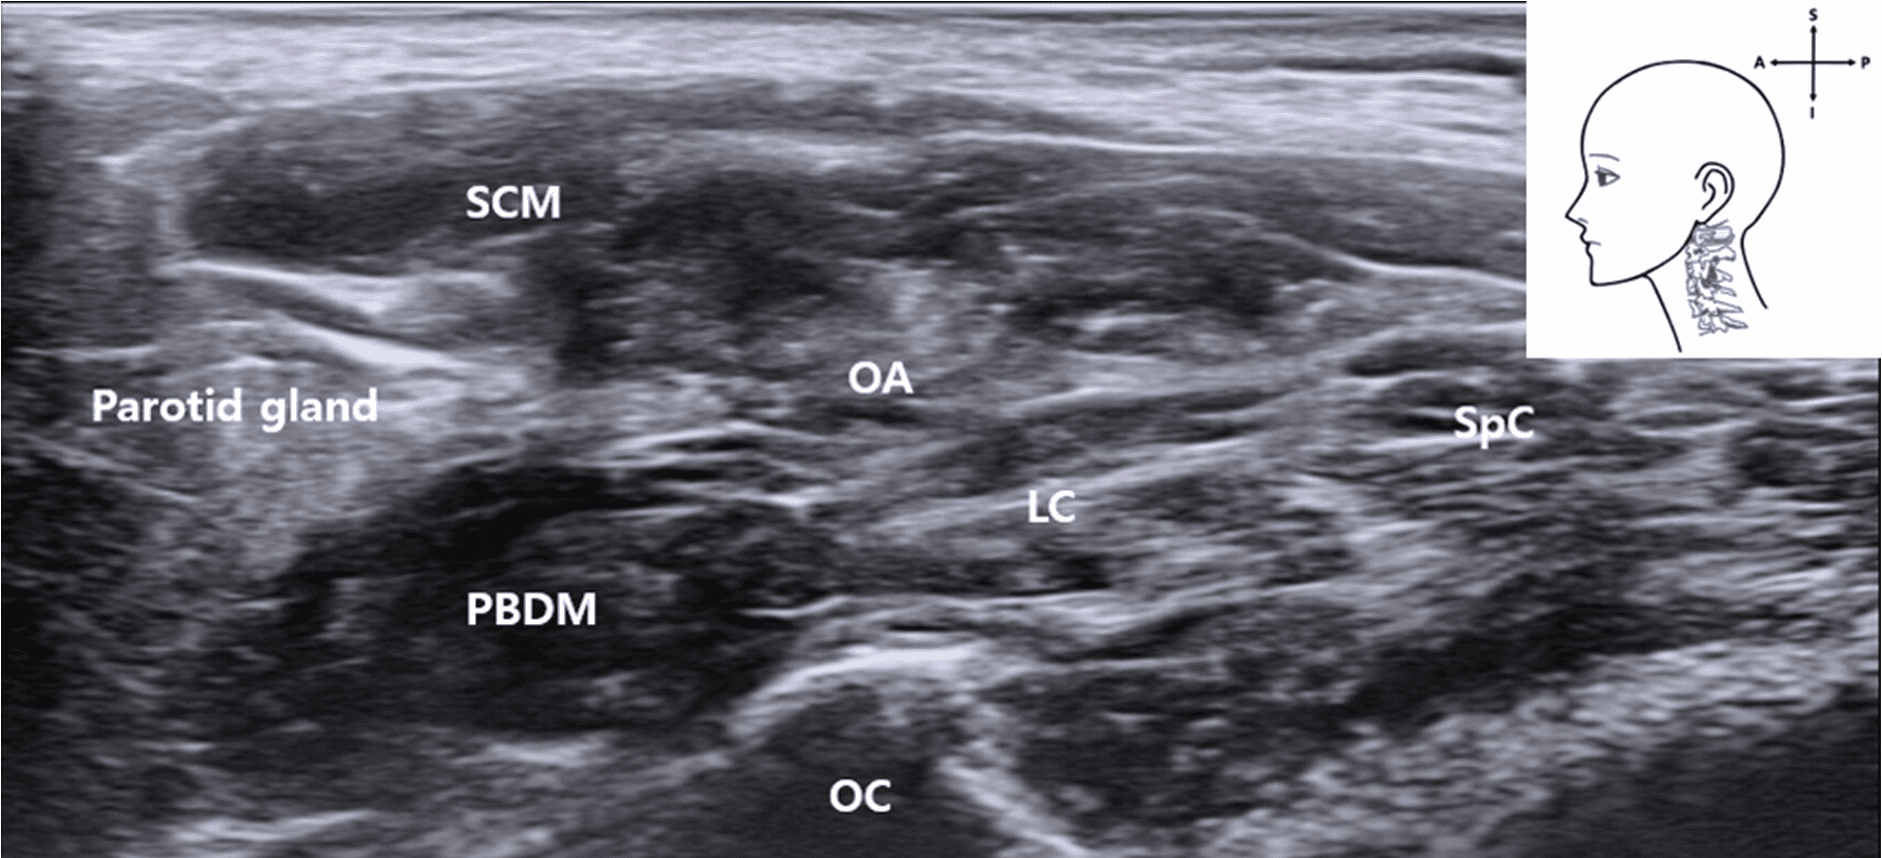

안면마비 - Ultrasound   image   corresponding   to   the   anatomical   dissection   of   t 안면마비 - Ultrasound   image   corresponding   to   the   anatomical   dissection   of   t Figure 2. Ultrasound image corresponding to the anatomical dissection of the right lateral neck showing key muscular and bony landmarks related to C1 identification and FN approach. SCM , sternocleidomastoid muscle; SpC , splenius capitis muscle; LC , longissimus capitis muscle; OCI , obliquus capitis inferior muscle; PBDM , posterior belly of the digastric muscle; C1 TP , transverse process of the atlas (C1); C1 Lamina , lamina of the atlas (C1); blue rectangle, probe position.